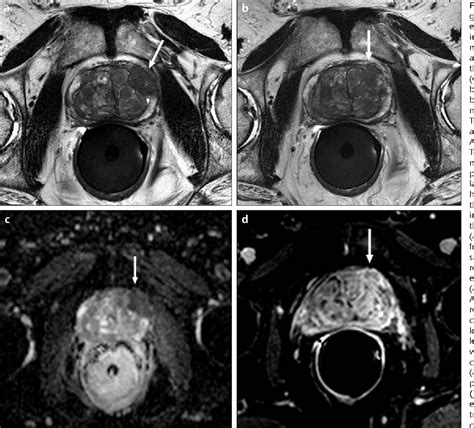

The diagnostic process typically involves three specific sequences that make up the "multi-parametric" aspect of the scan:

• T2-Weighted Imaging: Provides high-resolution anatomical details of the prostate structure.

• Diffusion-Weighted Imaging (DWI): Measures the movement of water molecules in the tissue, which is often restricted in malignant tumors.

• Dynamic Contrast-Enhanced (DCE) Imaging: Monitors how a contrast agent flows into the tissue, helping to highlight areas with abnormal blood vessel growth typical of cancer.